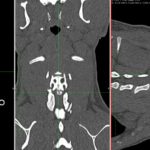

フレンチブルドッグは椎間板ヘルニア(IVDD)の好発犬種です。頸部痛、ふらつきのある患者さんにCT検査でC3~C4に大きな椎間板ヘルニアが確認されました。今回の責任病変です。顕微鏡下、Ventral Slotにより逸脱した椎間板物質を摘出しました。一般的な予後は大変良好です。